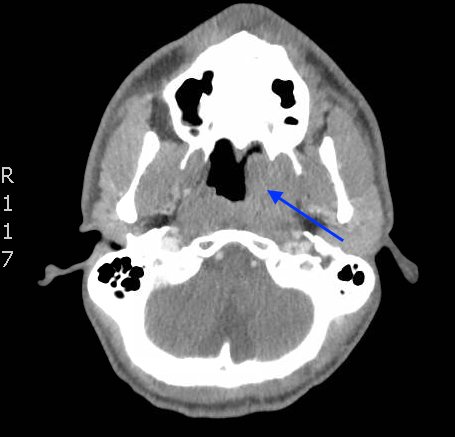

The photograph demonstrates an area of ulcerative tissue at the left palatine tonsil without surrounding erythema or purulent drainage. The computed tomography (CT) scan shows a large ulceration of the left soft palate and palatine tonsil (red arrow). There is no evidence of skull base osteomyelitis. There is suppurative lymphadenopathy with partial left jugular vein compression due to mass effect (yellow highlight). There is mild nasopharyngeal airway narrowing with architectural distortion (blue arrow), but no other evidence of airway obstruction.